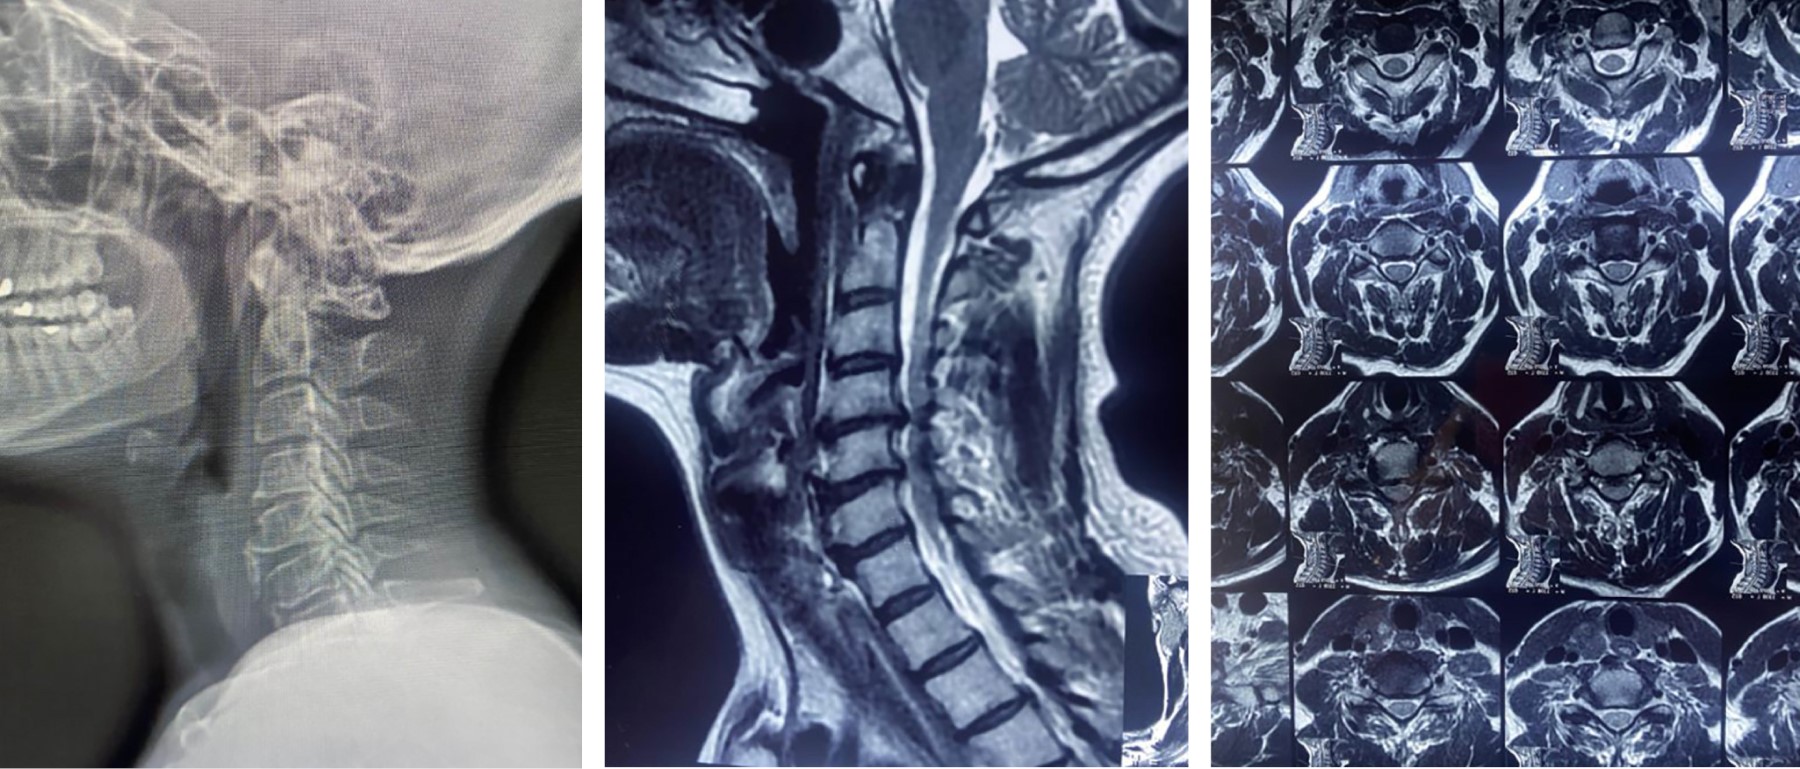

Según Kim, los síntomas clínicos suelen aparecer después de los 40 años, a medida que progresan los cambios degenerativos y son aproximadamente 50% más comunes en hombres que en mujeres, los cuales varían según el segmento cervical afectado y el grado de compresión. Los pacientes tienen un curso de la enfermedad que causa deterioro lentamente y causando parestesia general de las extremidades superiores y torpeza de las manos.7 La presentación clínica suele ser bimodal, con características únicas entre jóvenes y ancianos. Los pacientes más jóvenes sufren el síndrome de médula central debido a lesiones de alta velocidad, como accidentes de tráfico o lesiones deportivas. El síndrome en este grupo de edad puede ocurrir debido a una columna vertebral inestable, un prolapso de disco traumático o debido a una lesión del cuello por hiperextensión en un canal estrecho congénito ya estenosado. La población de edad avanzada presenta lesiones debido al movimiento relativo del cuello y la cabeza con el tronco (lesión por latigazo cervical y por hiperextensión (Figura 1).8

La evaluación radiográfica consiste en vistas ortogonales de la columna cervical con la boca abierta para determinar cualquier fractura de la región C1 y C2. Una angulación de más de 11° y una traslación de > 3.5 mm de una vértebra sobre la adyacente se considera inestable. Para las lesiones que son estables en la evaluación radiológica, la estabilidad se puede confirmar mediante radiografías dinámicas, el desplazamiento facetario, cifosis discal segmentaria local, aumento interespinoso la distancia y la anterolistesis son los criterios de inestabilidad dados por Roy Camillie. Cualquier fractura que no se vea en las radiografías o que sea dudosa en las radiografías se puede confirmar con una tomografía computarizada, lo cual proporciona una mejor comprensión de la alteración de la anatomía ósea.8

En cuanto a la resonancia magnética, ésta es más útil para determinar la afectación de los tejidos blandos y los cambios en el conducto medular y se considera la mejor modalidad. Las secuencias ponderadas en T2 y STIR son importantes para evaluar la lesión del disco, además de valorar la inestabilidad ligamentosa oculta hasta dentro de las primeras 48 horas del traumatismo.8,9 Entre los hallazgos en RM cabe destacar lo siguiente:9

- 1. La lesión del complejo ligamentoso posterior y la lesión de la médula pueden observarse como señales hiperintensas.

- 2. La presencia de intensidad prevertebral también puede ser otro signo de inestabilidad.

- 3. La presencia de una señal hipointensa rodeada por un halo hiperintenso en imágenes potenciadas en T2 se observa en casos de hemorragia del conducto medular, lo cual es un indicador de mal pronóstico para el resultado neurológico.

Por hallazgos radiológicos en resonancia magnética 14 (93%) presentaron protrusión discal, nueve (60%) osteofitos, cuatro (27%) hipertrofia ligamento amarillo, uno (7%) hipertrofia facetaria, seis (40%) esclerosis subcondral, uno (7%) fusión vertebral, siete (47%) mielomalacia y uno (7%) pérdida de la lordosis cervical.